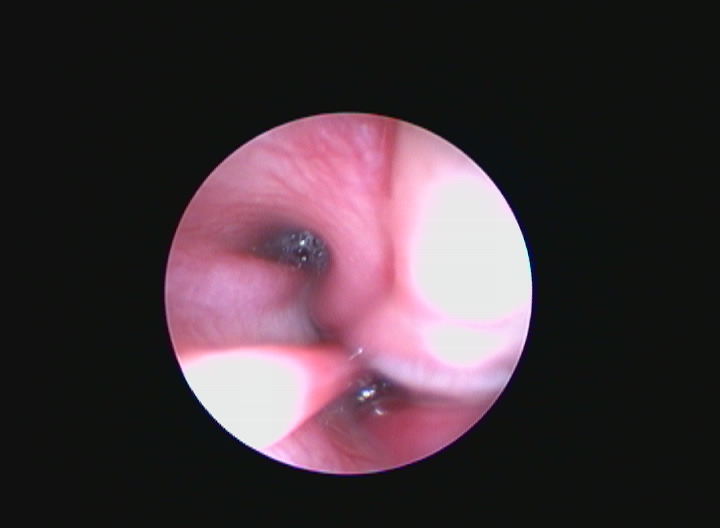

L'Endoscopia è una branca della diagnostica per immagini che permette di ottenere immagini fotografiche e filmati attraverso l'utilizzo di piccole telecamere.

L'Ospedale degli animali è in grado di eseguire esami endoscopici, quali gastroduodenoscopia, colonscopia (con prelievi bioptici) ed endoscopia delle vie respiratorie comprensive di BAL, brushing (per la citologia diagnostica ) e biopsia. La videondoscopia è una tecnica rapida e sicura e che spesso si coniuga con la chirurgia delle vie respiratorie.